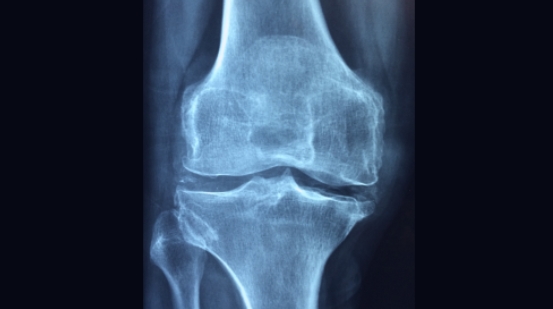

무릎관절은 인체에서 가장 중요한 관절 중 하나입니다. 그러나 무릎이 약해지면 무릎관절에 통증이나 불편함을 느낄 수 있는데요. 무릎관절이 약해지는 대표적인 원인은 노화이며, 외에도 과도한 운동, 비만, 외상 등이 있습니다.

원인의 대부분이 무릎 관절에 근육 조직이 부족하여 발생하기 때문에, 평소 무릎관절에 무리가 없는 좋은 운동으로 관리하는 것이 좋습니다. 이번에는 무릎관절에 좋은 운동에 대해서 자세히 알아보겠습니다.